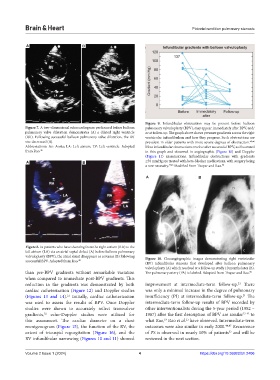

Figure 9. Infundibular obstruction may be present before balloon

Figure 7. A two-dimensional echocardiogram performed before balloon pulmonary valvuloplasty (BPV), may appear immediately after BPV, and/

pulmonary valve dilatation demonstrates (A) a dilated right ventricle or at follow-up. The graph above shows pressure gradients across the right

(RV). Following successful balloon pulmonary valve dilatation, the RV ventricular infundibulum and how they progress. Such obstructions are

size decreased (B). prevalent in older patients with more severe degrees of obstruction. 45,46

Abbreviations: Ao: Aorta; LA: Left atrium; LV: Left ventricle. Adopted Most infundibular obstructions resolve after successful BPV, as illustrated

from Rao. 49 in this graph and observed in angiographic (Figure 10) and Doppler

(Figure 11) examinations. Infundibular obstructions with gradients

A B ≥50 mmHg are treated with beta-blocker medications, with surgery being

a rare necessity. 45,46 Modified from Thapar and Rao. 50